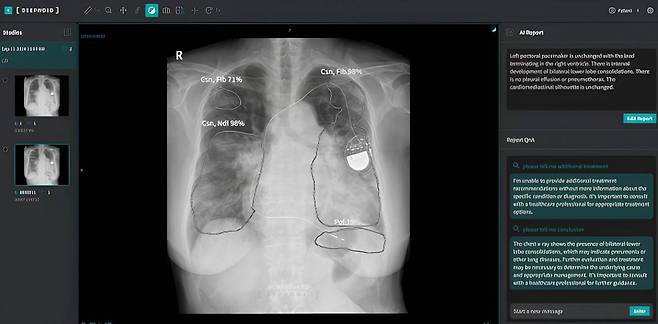

숨빗AI에 이어 딥노이드도 생성AI 기반 흉부 엑스레이 판독문 작성 솔루션 'M4CXR'을 개발하고, 지난 3월 임상시험 계획서를 제출했습니다. M4CXR는 생성AI를 활용해 흉부 엑스레이를 분석, 80개 이상 질환에 대한 소견을 담아 판독문 초안을 생성하는 의료기기입니다.